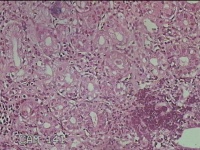

胃角粘膜

性别

男

年龄

29岁

临床诊断

复合性溃疡;慢性胃炎

一般病史

上腹部疼痛1个月余。

标本名称

大体所见

灰白粉红色组织小米大2团。

良性病变。